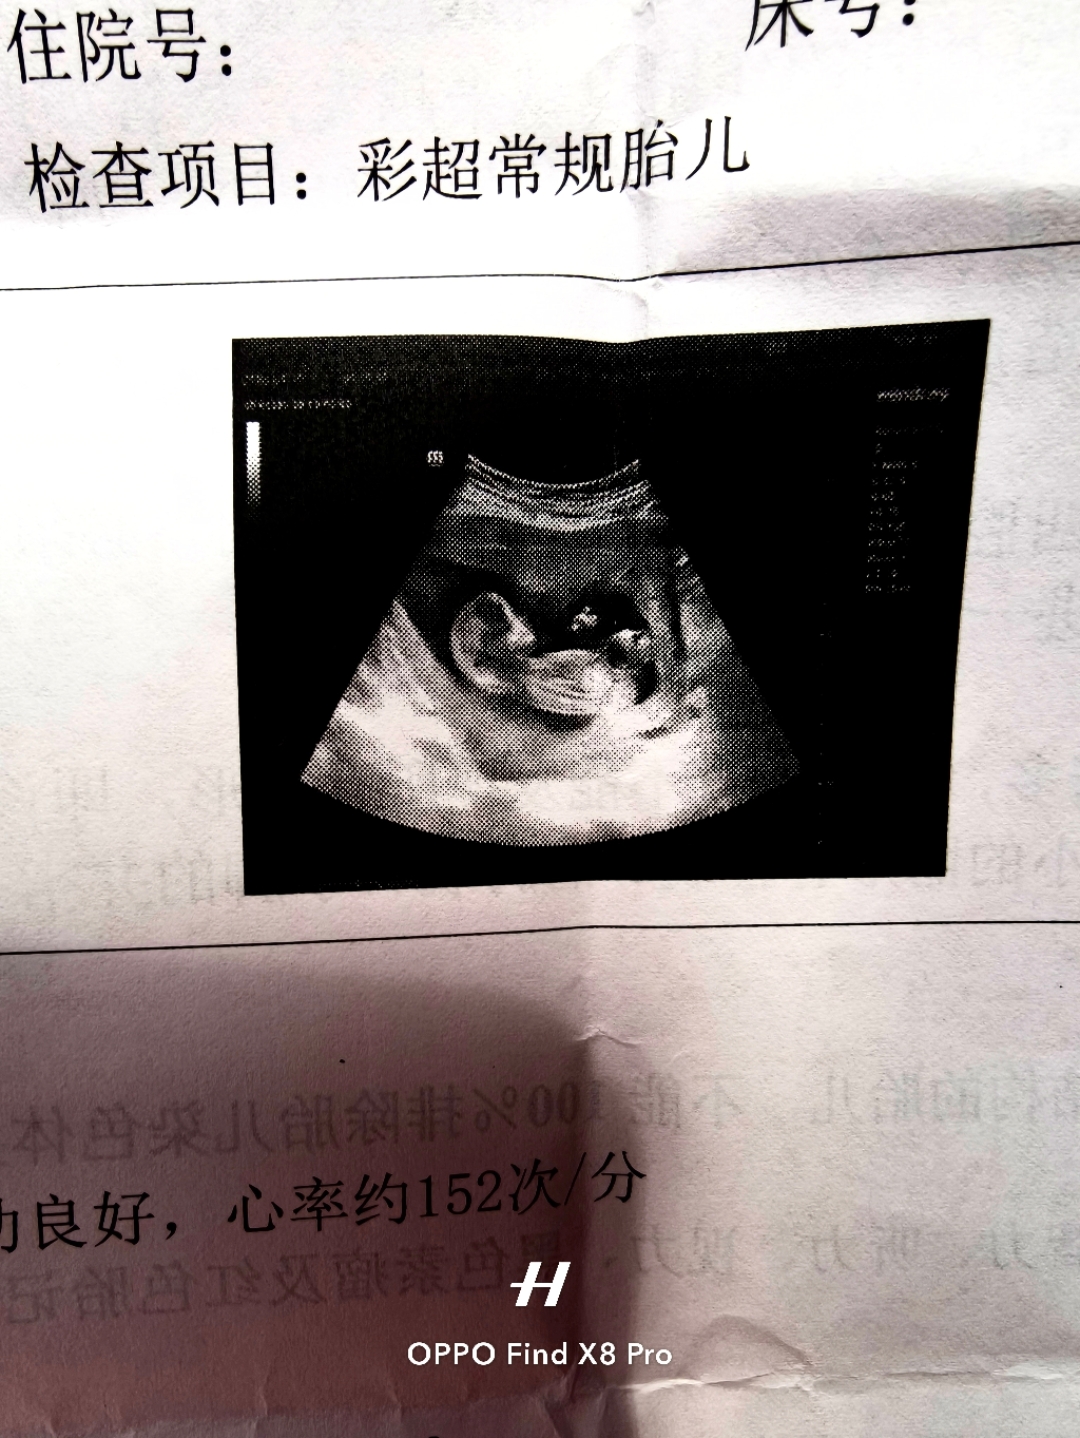

孕晚期的产检简直就是一场心理战。昨天刚做完B超,医生看着单子上的双顶径和腹围,轻描淡写地甩下一句偏大,注意控制饮食。就这短短几个字,直接把我的快乐剥夺了。从那天起,我彻底跟甜食、奶茶说了拜拜。看到同事喝冰奶茶,我只能默默给自己点一杯不加糖的柠檬水骗骗嘴巴。平时最爱的甘蔗、砂糖橘连碰都不敢碰,实在馋得受不了,就洗几颗普罗旺斯小番茄当水果吃。更折磨人的是早晨,明明饿得抓心挠肝,却不敢痛痛快快炫两个肉包子,每天都在跟自己的食欲作斗争。网上到处都是教人怎么长胎不长肉的攻略,好像孕期胖了就是罪过一样。可人这一辈子都在控糖,难道连在肚子里当个胎儿都要跟着受罪。孕妈的情绪稳定本来就难,如果连最基本的一点口腹之欲都要被剥夺,这种压抑的孕期真的毫无幸福感可言。我已经决定放过自己了,适当少吃点主食可以,但绝对不再盲目苛求体重,毕竟一个开开心心的妈妈比什么冷冰冰的检查数据都重要。